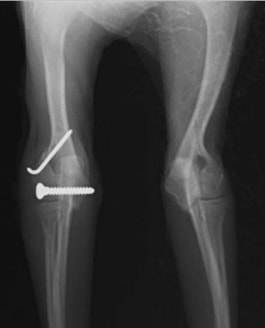

症例3:キルシュナーワイヤーのピンニングによる整復

ペルシャ猫 11ヶ月齢 雄

他院にて左大腿骨遠位の成長板骨折(salter-harrisⅠ型)が認められており、治療相談を目的として来院。当院にて、キルシュナーワイヤーを用いたピンニングにより骨折部位の整復を行いました。術後の経過は良好で、現在も経過観察中です。

術前レントゲン

術後レントゲン

機器

Arthrex社のターゲティングデバイスを用いてピンニングの位置を調整することで、確実な固定を行っています。当院ではこの手術器具以外にも、人の手術にも使用される様々な器具を導入し、手術精度を高め、また医療メーカーと新しい器具の開発、試作にも取り組んでおります。